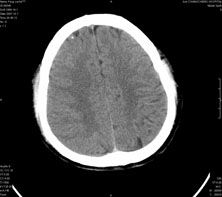

男,41岁,间断抽搐1小时,失神5分钟,bp130/90mmhg。低密度区ct值约16hu。

脑实质见多发散在的钙化点,左顶叶见一囊变灶,多考虑脑囊虫。

脑实质见多发散在的钙化点,右颞、顶叶见囊性灶,考虑脑囊虫。

多发的囊泡(多发囊型)+多发的钙化(慢性钙化型)=混合型

顶叶最大的囊直径2.2cm,如果考虑囊虫的话,囊是不是有点儿太大了?